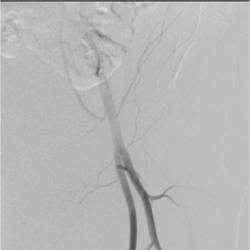

Gallery of Unlabled Radiographs from Lecture (Dr. French) - 2020

Click a thumbnail to enter the gallery display. Click the file name link at the bottom left of the gallery display to view the image at high resolution.